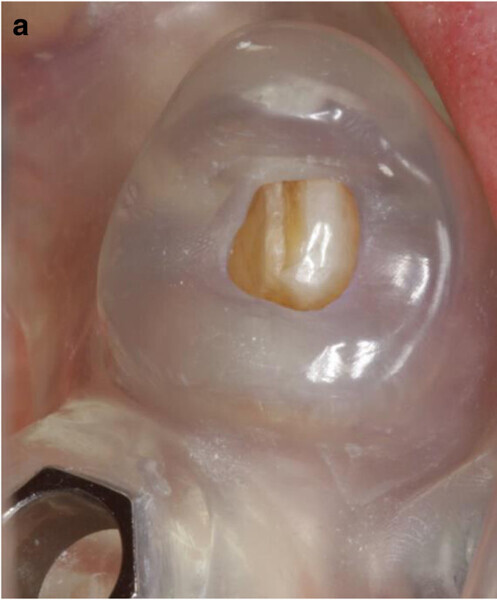

Fig. 6a: Occlusal view showing CAD of the provisional FDP framework (a) and close-up views from the interface between the CAD framework and the prefabricated titanium abutments (b & c).

Fig. 6b: Occlusal view showing CAD of the provisional FDP framework (a) and close-up views from the interface between the CAD framework and the prefabricated titanium abutments (b & c).

Fig. 6c: Occlusal view showing CAD of the provisional FDP framework (a) and close-up views from the interface between the CAD framework and the prefabricated titanium abutments (b & c).